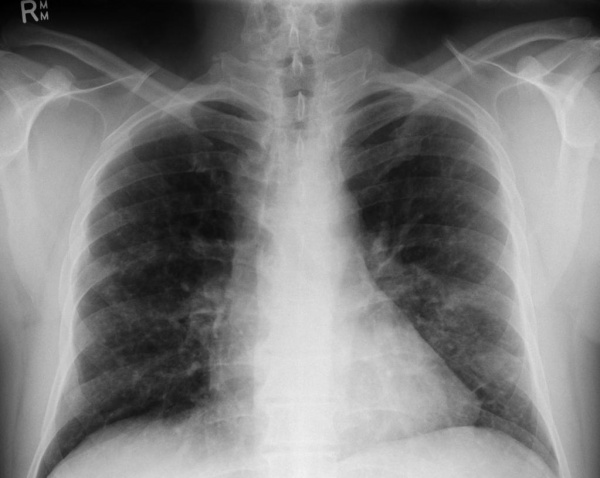

- Инструментальные исследования. При рентгенографии скелета находят очаги деструкции и остеолизиса, особенно выраженные в плоских костях черепа и длинных трубчатых костях. На рентгенограмме органов грудной клетки видны двусторонние мелкоочаговые затемнения (узелки, буллы), усиление легочного рисунка. Для более точной визуализации легочной ткани назначается компьютерная томография легких высокого разрешения, позволяющая определить их ячеистую деформацию. Результаты измерения функции внешнего дыхания (спирографии) показывают ухудшение диффузионной емкости легких.

Рентгенография легких. Диффузные двусторонние узловые затемнения и небольшие кисты в верхней и средней доле